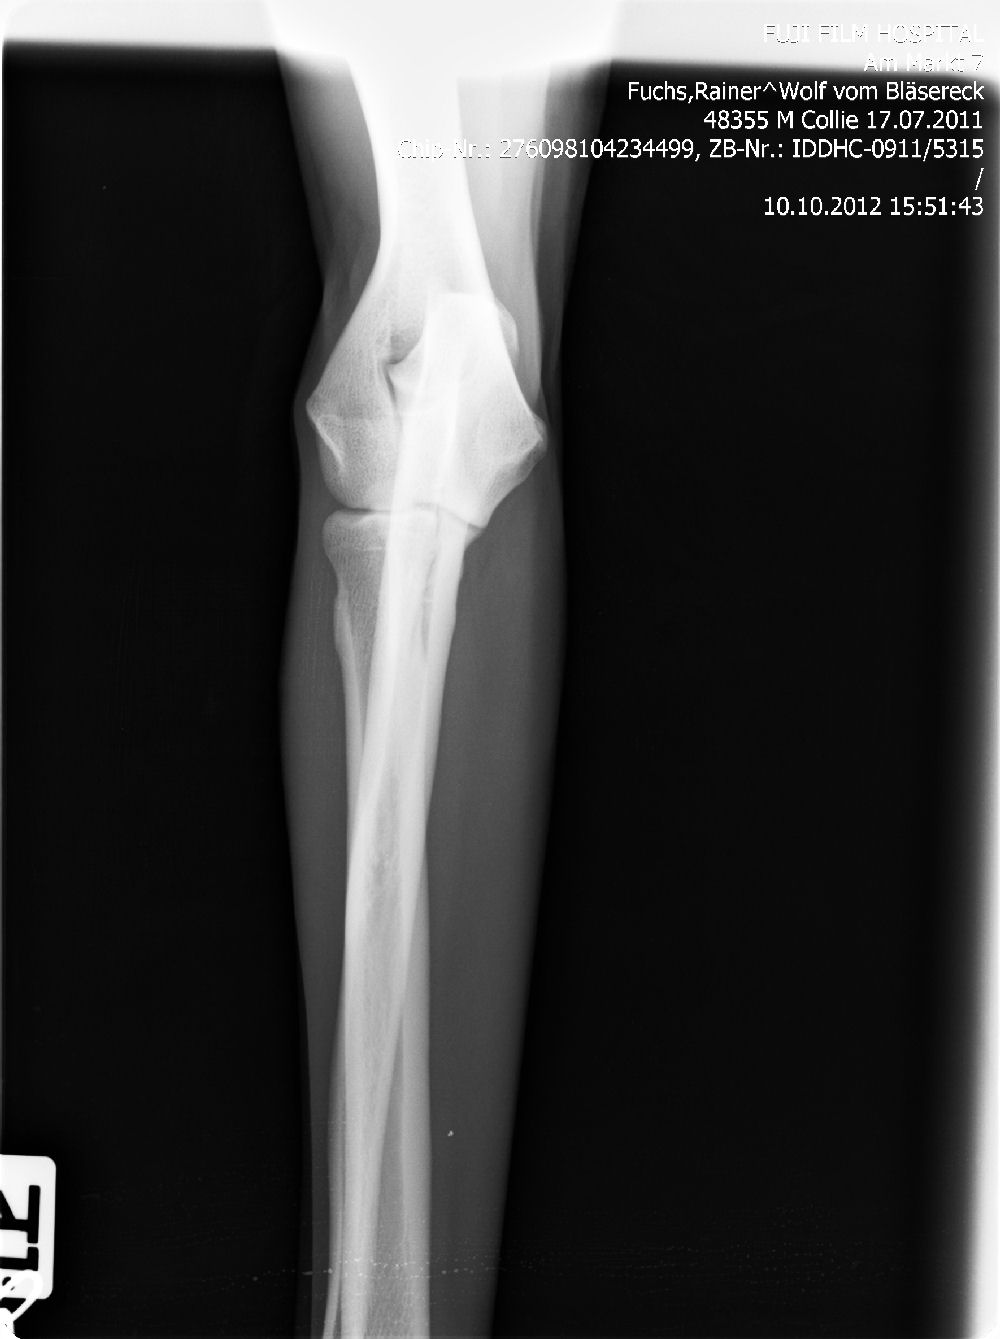

Ab dem Jahr 2008 wird nur noch Digitales Röntgen durchgeführt, da wir auch hier wieder führend und transparent sind, zeigen wir gern die Röntgenbilder ! Bei Züchtern, die dies nicht tun, haben Sie weniger Sicherheit !